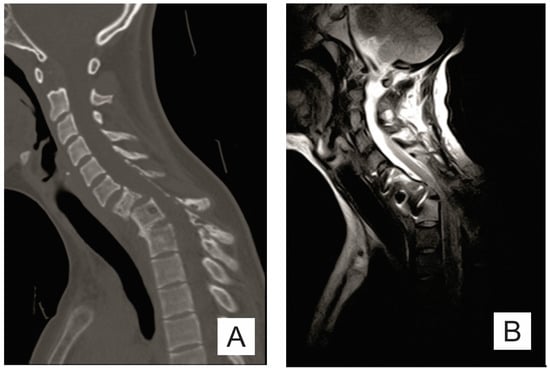

2. Case Report

| Month I | C7 corpectomy and reconstruction with autologous graft from the iliac crest, macroscopic resection of the posterior arches C7-T1 and fixation with C4-C5-T3-T4 cervico-thoracic hybrid system |

| Month III | Ablation of osteosynthesis material and bone graft and T1 corpectomy, reconstruction with C6-T1 mesh fixed with proximal and distal screw |

| Month IX | Ablation of damaged osteosynthesis material mesh C6-T1, ablation of thoracic screws, and introduction of bilateral T3, T4, and T5 screws |